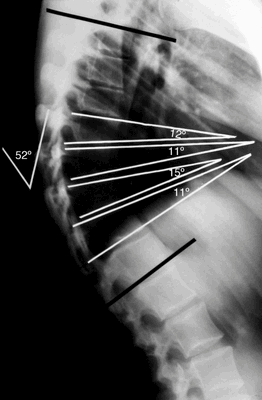

Рентгенограмма в боковой проекции

Согласно Sorenson, кифоз Шейермана характеризуется следующими критериями:

- Три или более соседних позвонков имеют клиновидную деформацию ≥ 5 градусов.

- Отсутствуют врожденные патологии позвоночника, а также его инфекционные заболевания и травмы.

Для оценки кифоза Шейермана необходимы тщательно собранный анамнез, физикальное обследование и рентгенограммы в боковой и передне-задней проекциях. Боковые рентгенограммы требуются при диагностике. Диагностическими критериями являются:

- Грубый гиперкифоз более чем 40 градусов.

- Передняя клиновидная деформация тела позвонка на 5 градусов или более (в трех или более соседних позвонках).

Также на рентгенограммах обнаруживаются:

- Неправильная форма у опорных площадок тел позвонков.

- Грыжи Шморля.

- Снижение высоты межпозвонкового пространства.

Тела трех или более грудных позвонков при болезни Шейермана-Мау деформируются, становятся клиновидными (на боковых рентгенограммах они выглядят почти треугольными). Из-за изменения формы позвонков кифоз усиливается. Изгиб в грудном отделе позвоночника достигает 45-75 градусов.

При болезни Шейермана происходит структурная деформация тел позвонков и позвоночника в целом. При этом заболевании кифотический угол в грудном отделе составляет около 45-75 градусов. Кроме того, происходит клиновидная деформация трех и более соседних позвонков на 5 и более градусов. Клиновидные тела позвонков определяют природу гиперкифоза, который наблюдается при болезни Шейермана. Гиперкифоз может быть скомпенсирован поясничным или шейным гиперлордозом.